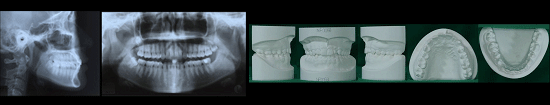

1) 진단

첫방문시 촬영한 X-ray사진과, 구내사진 및 얼굴사진, 치아모형등을 바탕으로 정확한 치료계획을 수립하게 되며 환자분에 적합한 교정치료방법을 결정하게 됩니다.

환자분의 자료를 과학적인 데이터베이스를 통해 분석하여 치료 계획을 정확히 수립해야 하므로, 교정진단 자료를 채득한 후, 빠르면 하루, 늦게는 2-3일 후에 교정 진단을 받게 됩니다.